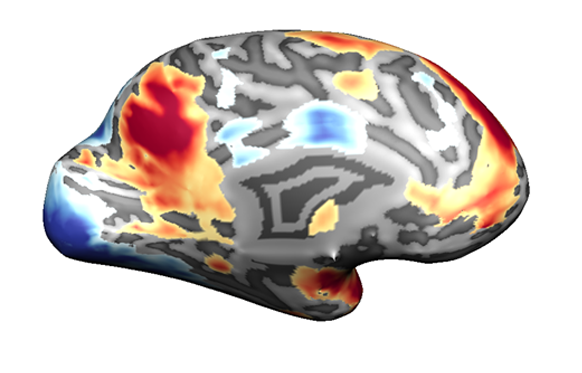

وفي مسائل أخرى، كأيّ مناطق من الدّماغ كانت نَشِطة أثناء الاختبار، كان هناك اتّفاق أكبر بين المجموعات المختلفة. وقد أثارت النّتائج جدلًا علميًّا حيويًّا، وأشارت إلى أنّه في عمليّة متعدّدة المراحل، لتحليل بيانات الـ fMRI، على الباحثين اتّخاذ قرارات عديدة فيما يتعلّق بحساب البيانات، واستخدام أدوات البرمجيّات المتاحة لهم، والاختبارات الإحصائيّة التي سيفحصون بها البيانات. تؤثّر هذه القرارات بشكل كبير على النّتائج والاستنتاجات.

لكل ڤوكسل، نود أن نفحص ما إذا كان هناك تغيير في الإشارة أثناء تنفيذ المهمة، مقارنة بمستوى الإشارة المقاس في ظروف المجموعة الضابطة. دماغ مع وحدات ڤوكسل تزيد من نشاطها (بألوان دافئة) وأخرى تقلّل من نشاطها (بألوان باردة) عندما تماهى المشاركون في التّجربة مع مشاعر الآخرين | الصّورة مقدّمة من د. عدي يانيف